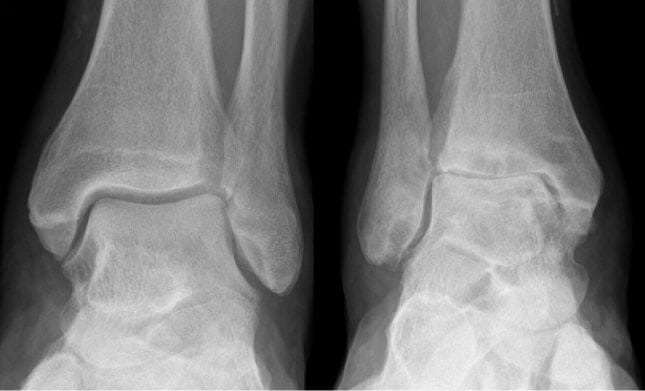

Признаки артроза хорошо визуализируются на рентгенологических снимках. Наблюдается сужение или сращение суставной щели, объединяющей берцовую и таранную кости. Это свидетельствует о значительном поражении всех хрящевых тканей. Методы консервативной терапии тут безрезультативны. Если сохранить сочленение артроскопическими методами лечения (санацией, трансплантацией хрящевых тканей) невозможно, то проводится эндопротезирование голеностопного сустава — его полная замена искусственным протезом.

Протезирование голеностопного сустава показано пациентам при деформирующем артрозе 3 степени и на 4 рентгенологической стадии. Но хирурги-ортопеды иногда рекомендуют замену сочленения больным со 2 степенью патологии. Это продиктовано быстрым прогрессированием остеоартроза, несмотря на все применяемые консервативные методы терапии — прием препаратов, ношение ортезов, регулярные занятия лечебной физкультурой. Пациента готовят к эндопротезированию при диагностировании следующих патологий: